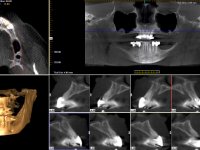

Realizada uma TAC, foi planificada a colocação de 6 implantes no maxilar superior. Foi decidida a colocação de dois implantes na zona dos incisivos centrais, dois implantes na zona dos caninos e dois na zona dos segundos pré-molares. A ausência de estrutura óssea na zona distal do primeiro quadrante implicava a realização de uma regeneração óssea no seio maxilar direito. A cirurgia foi realizada e após a colocação dos implantes foi feita a impressão para confeção de uma prótese provisória metalo-acrílica aparafusada para colocação em carga imediata no dia seguinte. O implante colocado na zona do seio maxilar direito não foi colocado em carga. Passados 6 meses foi realizada a impressão aos 6 implantes com técnica de moldeira aberta e foram confecionados os modelos de trabalho. Numa consulta seguinte foram montados os modelos de trabalho em articulador semi-ajustável utilizando o arco facial e a relação inter-maxilar obtida com a prótese provisória. Foi feita uma muralha de silicone sobre a ponte provisória com o objetivo de orientar o trabalho laboratorial. Realizada a infra estrutura metálica aparafusada esta foi provada em boca e finalmente após colocação de cerâmica o trabalho foi colocado definitivamente. Como passaram vários meses após a realização da primeira TAC foi feita uma segunda para planificar a colocação de implantes no 4º quadrante. Colocaram-se 3 implantes na mesma sessão em que foi feita a extração dos pilares da ponte. Estes implantes foram posteriormente reabilitados com uma ponte metalo-cerâmica aparafusada de três elementos.